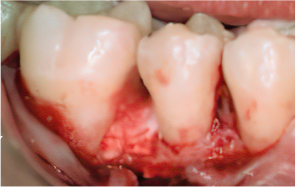

엠도게인 수술과정

STEP 01

잇몸을 절개

-

STEP 02

Scaling Root Planning을 실시

STEP 03

치석 및 치태 등 제거

STEP 04

엠도게인 도포